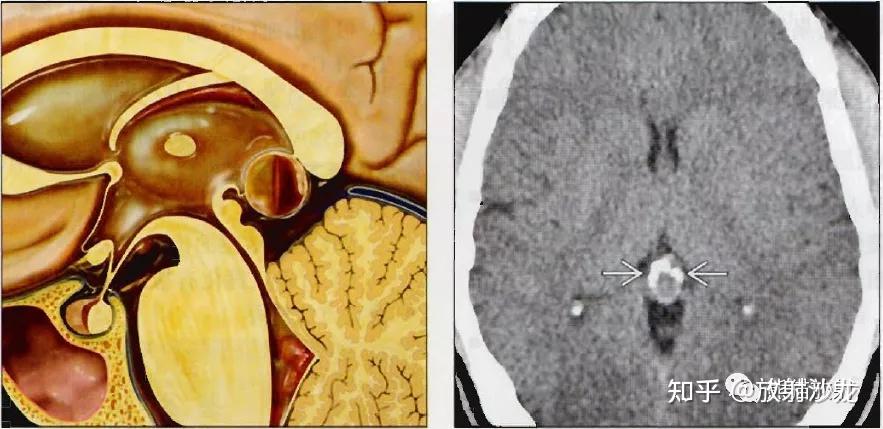

松果体は、脳にある小さなエンドウ豆の形をした腺です。専門家注記メラトニンや他のホルモンの分泌に重要な役割を果たします。

しかし、松果体腫瘍が発生すると、体の他の多くの部分に影響を与える可能性があります。これは、松果体が他の多くの重要な構造の近くに位置しており、血液やその他の体液と強く相互作用するためです。